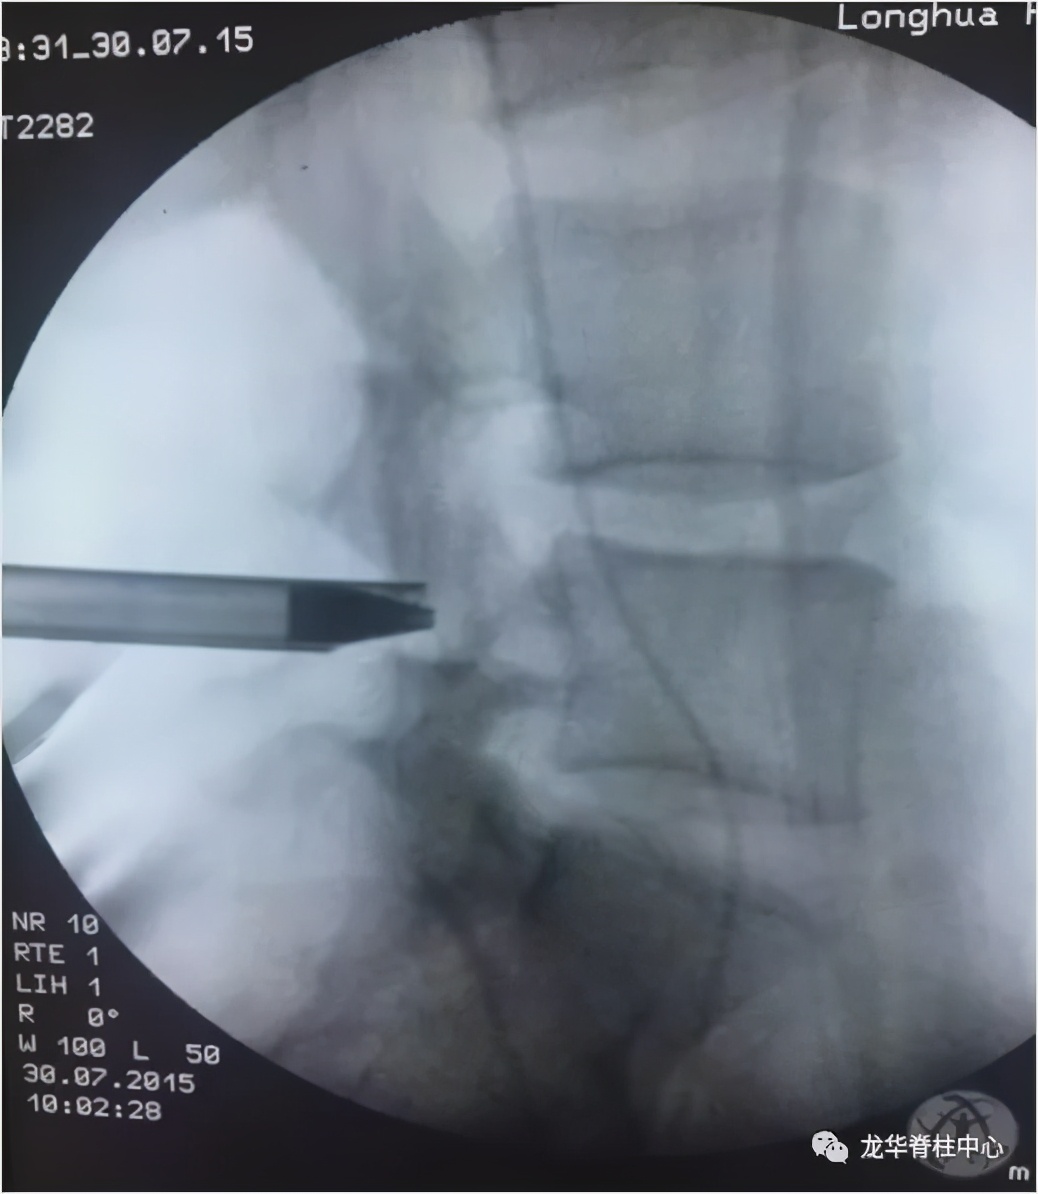

枢椎齿状突骨折前路空心钉固定术

微创经皮内镜下椎间盘摘除术